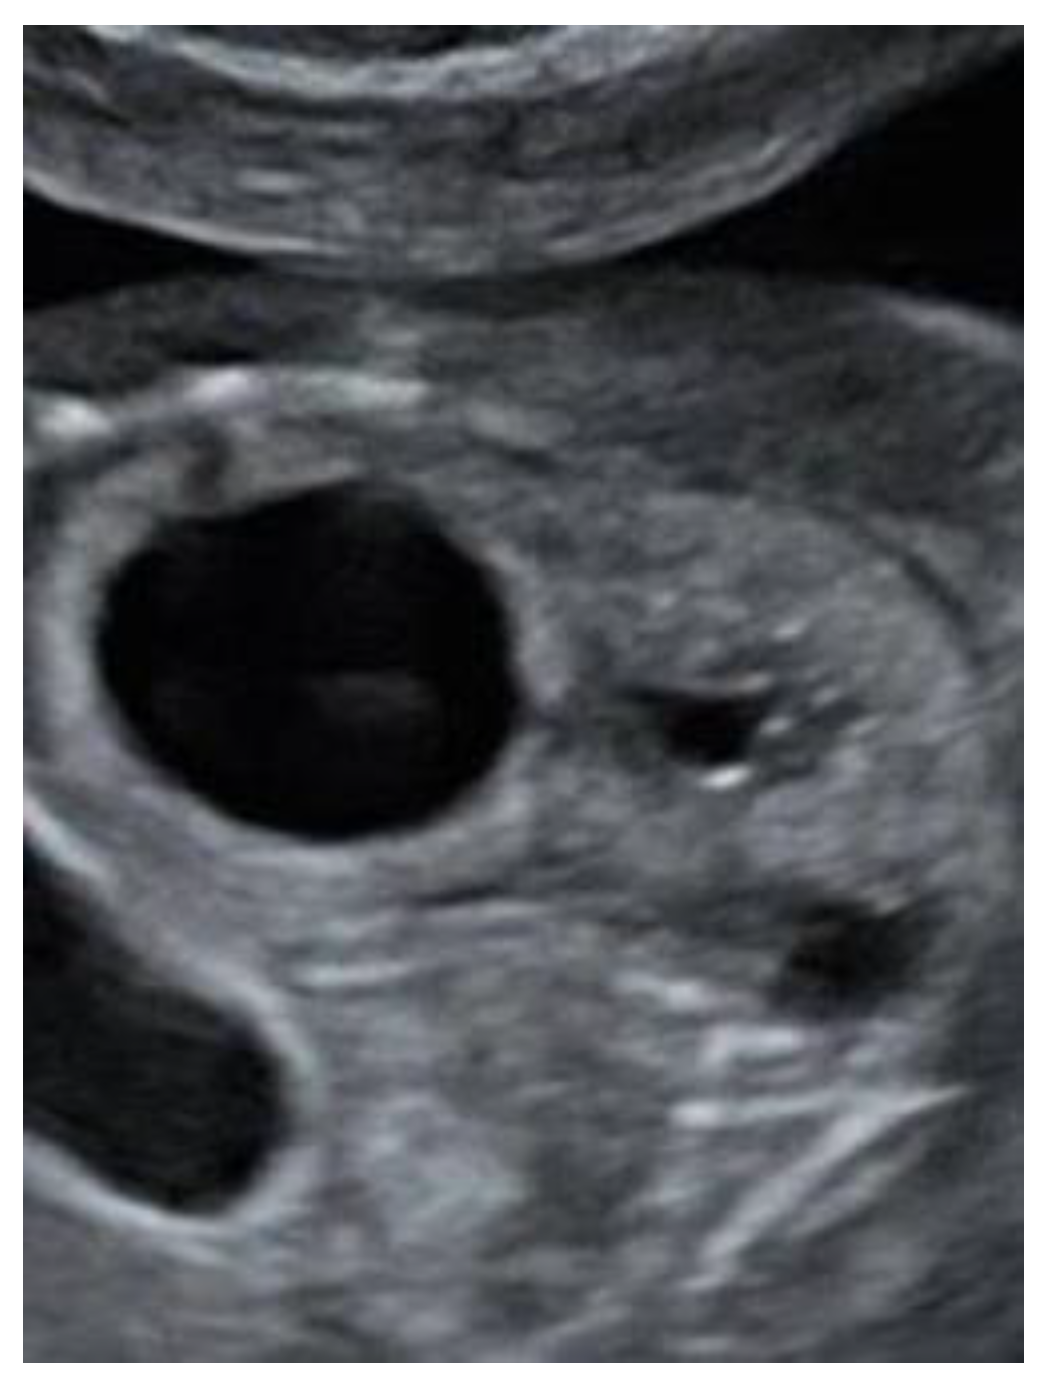

A 27-year-old primigravida was referred to the outpatient clinic of our hospital at a gestational age (GA) of 17 + 3 weeks following detection of a fetal unilateral hydronephrosis by the peripheral gynecologist. Ultrasonography demonstrated a duplex collecting system in the left kidney with hydronephrosis of the cranial pole, moderate dilatation of the upper pole ureter, and mild dilatation of the lower pole ureter. The cerebellum at that time showed a minimal posterior curving (

Figure 1), but no distinct banana-sign. Inspection of the spine was inconspicuous. The patient was reevaluated in our center at 24 weeks GA. The hydronephrosis of the upper pole of the left kidney remained stable. However, the cerebellum presented a banana-shape with herniation of the hindbrain onto C2 and minimal lemon-sign of the skull (